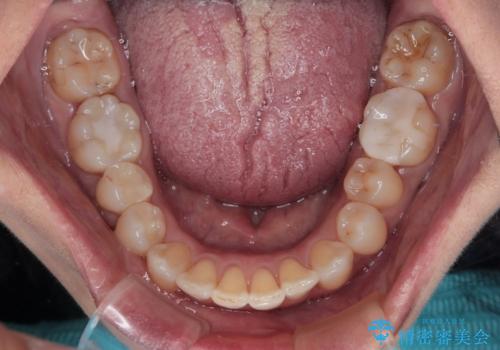

前歯のデコボコとむし歯治療の跡 インビザライン矯正とオールセラミッククラウン治療

デコボコの程度は中等度であったため、インビザライン・モデレートパッケージにて歯列を整えることとしました。

セラミッククラウンの装着されていた前歯と、大きな修復治療の跡がある反対側の歯は、矯正治療後に補綴治療を行うこととしました。

奥歯の欠損はインプラント、ブリッジ、入れ歯のどれにすれば良いかを決められず、仕事が非常にお忙しいこともあり、保留としたまま治療を終えることとなりました。

後戻りのリスクがあるため、なるべく早めに欠損補綴治療を開始する予定です。